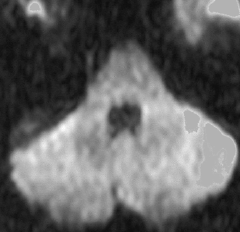

10代で発見された四丘体槽の類表皮のう胞です。左の画像,拡散強調像 DWIで真っ白に見えるので診断できます。真ん中は発見された時のもの,右側の画像は7年後です。ゆっくり増大してきたので,開頭手術(経テント法)で完全摘出しました。周囲の血管や神経に癒着するのでそれほど簡単な手術ではありません。

20代の女性が右の激しい顔面痛(三叉神経痛)で発症しました。左から順にMRIのT1強調画像,T2強調画像,拡散強調画像です。髄液と同じように見えますので脳の形の変形だけで腫瘍があることを疑います。でも,拡散強調画像では真っ白になるので腫瘍が存在していることがわかります。三叉神経は腫瘍の真ん中にあって伸びています。

術後の写真です。普通のMRIでは全部取れているかどうかわかりませんが,左の拡散強調画像をみるとおよそ全部取れていることがわかります。でも完全摘出の完全な証明は画像ではできません。術後10年くらい経ちますが再発はありませんでした。